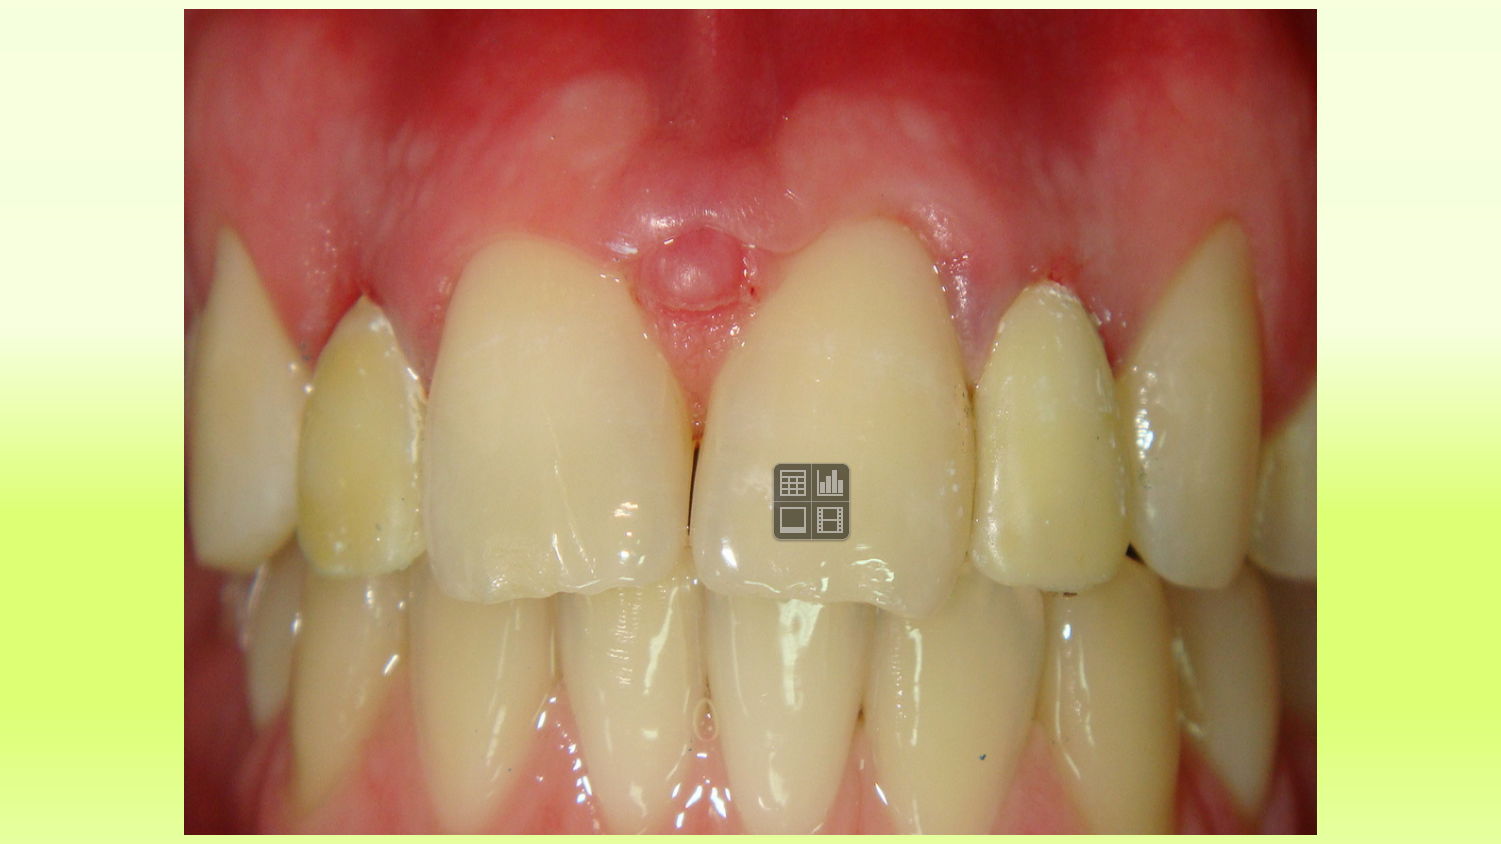

Case 12

“Vector” Implant placement in the area of 22 and 12 missing teeth is the only correct solution.